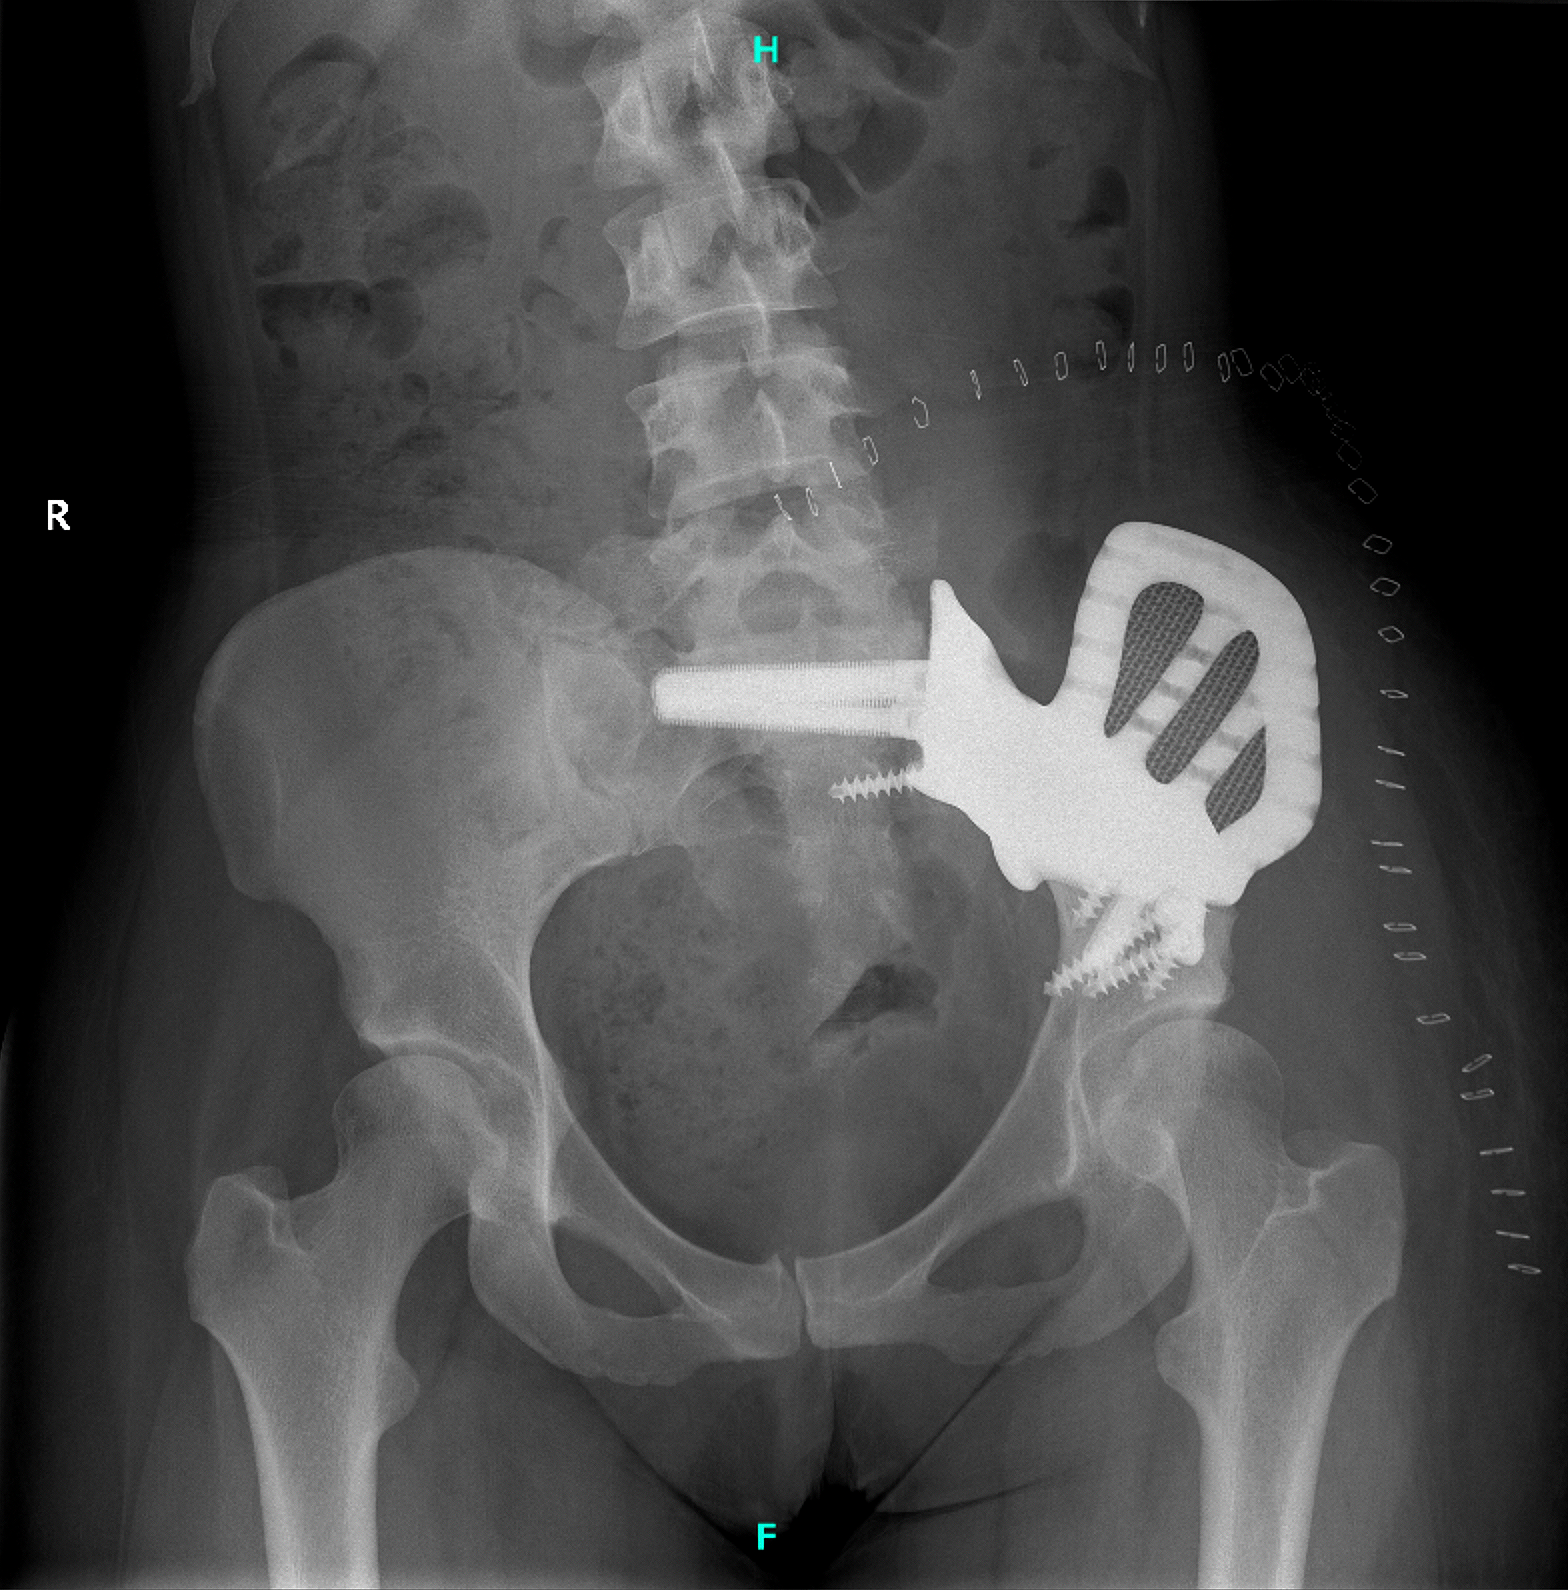

The patient’s recovery was uneventful. She was discharged after three weeks without any complications.

She was then initiated on partial weight-bearing, followed by structured rehabilitation. The implant provided

stable fixation, restored pelvic continuity, and preserved the native hip joint.

Figure 6: Postoperative anteroposterior pelvic X-ray confirming the correct positioning and fixation of the custom-made implant.